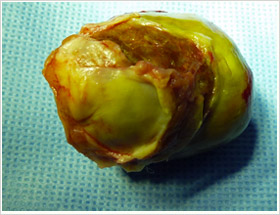

Elle se présentent sous deux aspects : la forme « gélatineuse » qui est à l’origine de complications emboliques systémiques au niveau des membres et du cerveau et la forme « fibreuse » arrondie et ferme qui est à l’origine des enclavements dans l’orifice mitral qui sépare l’oreillette et le ventricule gauche.

Les symptômes (essoufflements, toux, malaises voire syncope surtout aux changements de position) sont liés à la taille de la tumeur (qui varie de 1 à 8 cm de diamètre), à sa localisation par rapport à l’orifice mitral et aux veines pulmonaires, à son aspect (gélatineux ou fibreux) ainsi qu’à sa mobilité (tumeur villeuse ou pédiculée).

Sous circulation extracorporelle, le cœur et les poumons sont arrêtés. On ouvre l’oreillette gauche et on procède à l’ablation de l’intégralité de la tumeur sans la fractionner. On résèque la zone d’implantation qui siège le plus souvent au niveau de la cloison entre les deux oreillettes et qui est refermée par un patch de péricarde ou de Dacron.